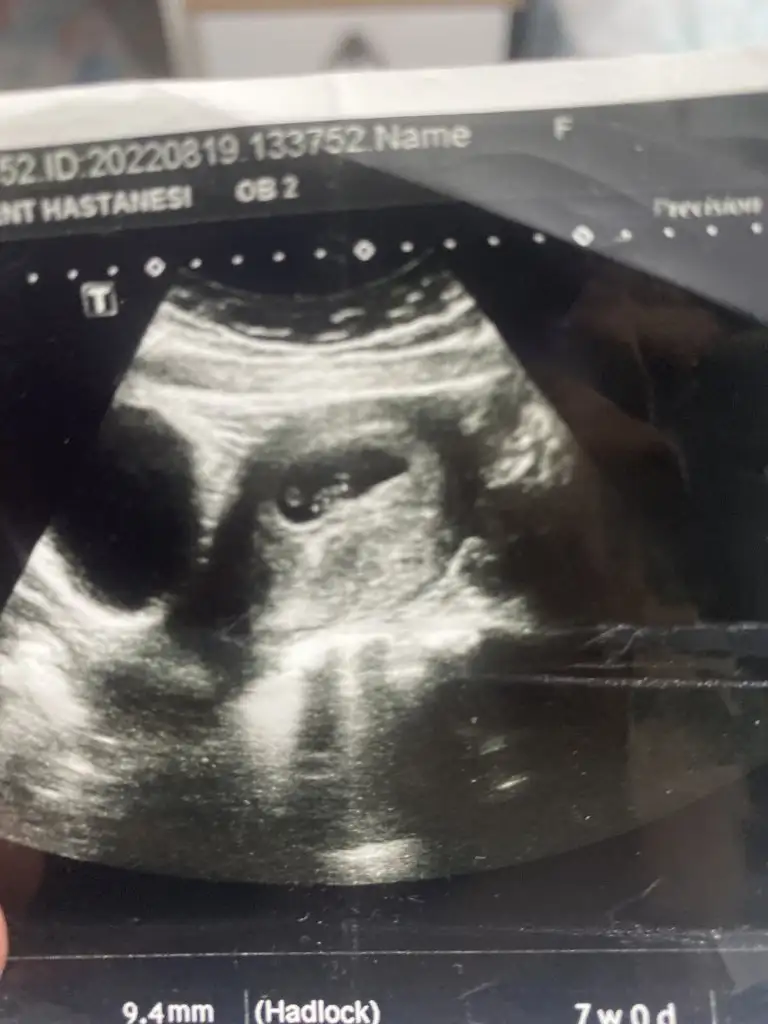

Bnce kesin erkek bakın nubu birbirine paralel değil paralel olsaydı kız olurdu 6 haftalık USG varmiBnmki nedir arkdsalar nubu cok net karar veremedim 10+3 gunluk burda vajinal bakildi

Evt buda 6 haftalik 7 de olbilirBnce kesin erkek bakın nubu birbirine paralel değil paralel olsaydı kız olurdu 6 haftalık USG varmi

Tmm hiç arasturmayin yüzde 200 erkekEvt buda 6 haftalik 7 de olbilir

Tesekkr edrim doktorum yarim saat bakti nuba gore kiza benzettim cikintisi asagida demisti ama bakalim hayirlisi hakkimizdaTmm hiç arasturmayin yüzde 200 erkeköğrenirseniz haber edin

Bakın anlayan var içinizde şüphe varsa netten bakın kızın ve erkeğin nubuna erkekle aynı ramziye göre de erkek Allah hayırlısını nasip etsin insTesekkr edrim doktorum yarim saat bakti nuba gore kiza benzettim cikintisi asagida demisti ama bakalim hayirlisi hakkimizda![]()

Tesekr edrim ogrenince yazarim suan 3 aylik olduk karindan bakildi dun farkli bi doktora gittim ama cinsiyet icin cok erken dedi doktor ikisindede cikinti oluyo oyuzden tahmin zor dedi 1 ay sonra cagardi kesin belli olur dedi bakalimBakın anlayan var içinizde şüphe varsa netten bakın kızın ve erkeğin nubuna erkekle aynı ramziye göre de erkek Allah hayırlısını nasip etsin ins

Grupta kız diyen olmaz yani bazı Dr anlamiyo gerçektenTesekr edrim ogrenince yazarim suan 3 aylik olduk karindan bakildi dun farkli bi doktora gittim ama cinsiyet icin cok erken dedi doktor ikisindede cikinti oluyo oyuzden tahmin zor dedi 1 ay sonra cagardi kesin belli olur dedi bakalim